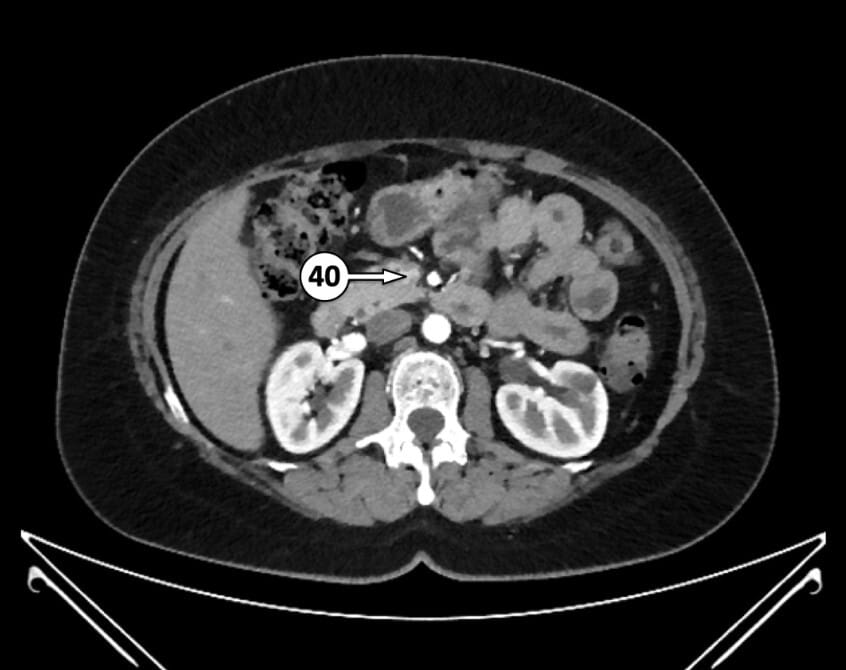

40. superior mesenteric vein